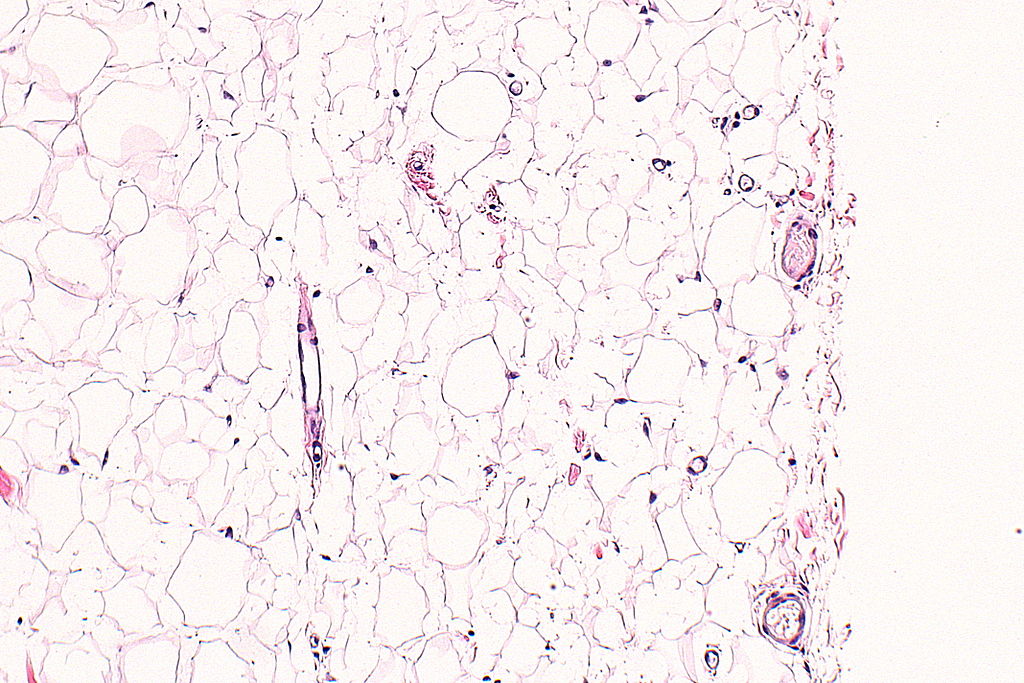

Nephron/Wikimedia Commons

Lipomi su benigne tvorevine sastavljene od masnog tkiva koje se obično formiraju između kože i mišića. Ovi dobroćudni tumori vezivnog tkiva najčešće se opisuju kao mekane, gumaste grudice koje se mogu pomicati pod pritiskom prsta. Važno je znati da lipomi nisu kancerogeni i u većini slučajeva ne predstavljaju zdravstveni rizik.

U rijetkim slučajevima, kada postoji sumnja da bi tvorevina mogla biti liposarkom, liječnik može preporučiti biopsiju. Tijekom ovog postupka, mali uzorak tkiva se uzima i analizira pod mikroskopom kako bi se utvrdila priroda tvorevine.